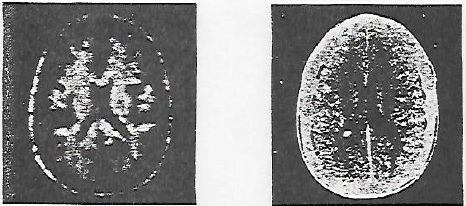

Sur la figure 18 on observe la région lombaire, sur la figure 19 le cœur, et sur la figure 20 la comparaison entre une image obtenue par tomographie et une image obtenue par RMN.

Fig. 18. LA RÉGION LOMBAIRE de la colonne vertébrale d’un patient est obtenue par reconstructions à partir d’un ensemble de données de RMN tridimensionnelles. L’image de gauche représente une coupe passant par la moelle épinière, dans la colonne vertébrale. Sur l’image de droite, on a déplacé le plan de l’image de quelques centimètres afin d’observer les disques intervertébraux.

Ces images sont habituellement très difficiles à obtenir sur une aussi grande surface par tomographie ou par toute autre méthode d’imagerie. Elles ont été réalisées par les chercheurs de la société Technicare.

Fig. 19. ON OBSERVE LE CŒUR en faisant des coupes transversales d’une poitrine humaine par RMN (les deux formes plus petites de chaque côté de la poitrine sont dues aux bras). L’image de gauche représente le cœur à la fin d’une systole, quand les ventricules se sont vidés. L’image de droite montre la fin d’une diastole, quand les ventricules sont pleins. Ces images, fournies par la société Technicare, ont été réalisées en synchronisant la prise de données avec le cycle cardiaque.

Fig. 20. UNE IMAGE DE RMN donne plus de renseignements sur les tissus lésés qu’une image par tomographie aux rayons X, comme on le voit sur ces deux coupes transversales du cerveau d’un patient atteint d’une tumeur cérébrale. Sur l’image de RMN (à gauche), obtenue à partir de données en trois dimensions, la tumeur est la zone circulaire sombre du côté droit du cerveau. Sur l’image obtenue par tomographie (à droite), la tumeur n’apparaît pas. Ces images, réalisées à l’Hôpital Central du Massachussetts, sont reproduites avec l’autorisation du Journal of Computerized Axial Tomography.